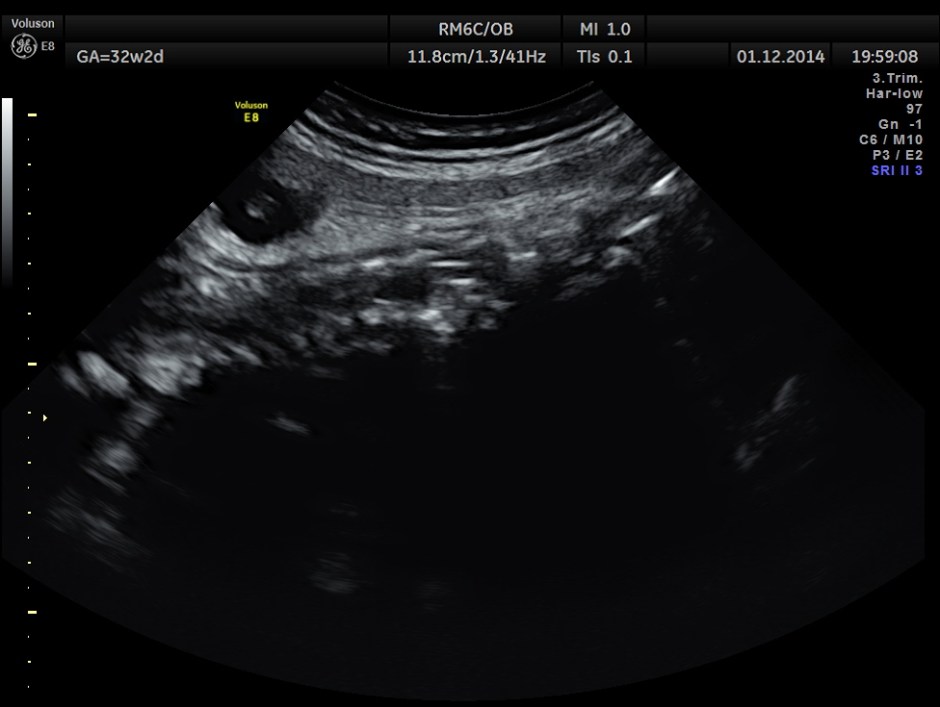

Hydrocephalus is seen ; Cisterna magna appeared somewhat compressed.

Spinal deformity was also noted.